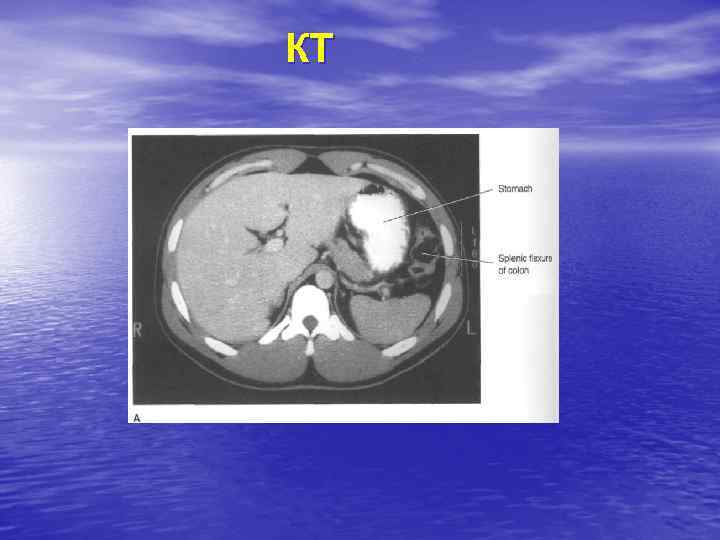

КТ

КТ-семиотика • Форма, размеры, положение, контуры • • • печени. Локализация участков поражения, их количество, денсивность (изо-, гипер-), форма, размеры, контуры, структура, состояние окружающих органов.

Очаговые поражения ВС: Увеличение печени, участок с измененной структурой паренхимы (гипо-, гиперденсивный, неоднородный). МС –объемное образование - опухоль, метастаз, эхинококковая киста